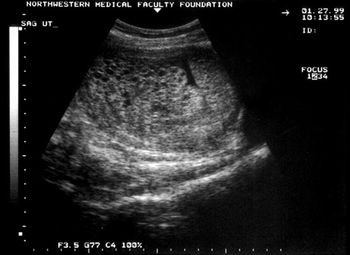

Ultrasonography plays a critical role in the diagnosis of both complete and partial molar pregnancy.